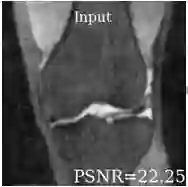

Deep learning based techniques achieve state-of-the-art results in a wide range of image reconstruction tasks like compressed sensing. These methods almost always have hyperparameters, such as the weight coefficients that balance the different terms in the optimized loss function. The typical approach is to train the model for a hyperparameter setting determined with some empirical or theoretical justification. Thus, at inference time, the model can only compute reconstructions corresponding to the pre-determined hyperparameter values. In this work, we present a hypernetwork based approach, called HyperRecon, to train reconstruction models that are agnostic to hyperparameter settings. At inference time, HyperRecon can efficiently produce diverse reconstructions, which would each correspond to different hyperparameter values. In this framework, the user is empowered to select the most useful output(s) based on their own judgement. We demonstrate our method in compressed sensing, super-resolution and denoising tasks, using two large-scale and publicly-available MRI datasets. Our code is available at https://github.com/alanqrwang/hyperrecon.